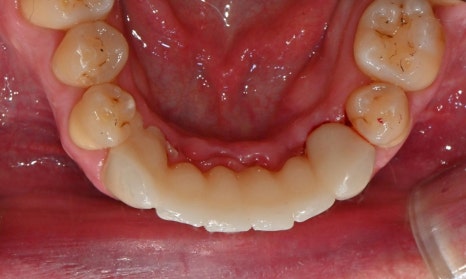

진단 결과, 교합시 하악 전치가 거의 보이지 않을 정도로 깊은 교합을 보이고 있었으며, 어린 시절 외상을 입었던 앞니는 치아 뿌리 부근에 광범위한 염증이 관찰되어 장기적인 유지가 어려운 상태였습니다. 이에 앞니 두 개는 발치를 결정하였고, 환자의 비교적 젊은 나이를 고려하여 가능한 한 최대한 치아를 보존하기 위해 앞니 부위 임플란트를 고려했습니다. 그러나 해당 부위 골 손실이 매우 심했고, 외국인 환자로 장기간 내원이 어려운 상황이었기 때문에, 광범위한 골이식을 동반한 임플란트 치료 보다는 비교적 짧은 기간 내에 기능과 심미를 회복할 수 있는 브릿지 보철 치료를 계획하였습니다.

또한 하악 전치가 혀 쪽으로 과도하게 쓰러져 있어 보철적으로 위치를 회복하기에는 한계가 있어, 발치 후 후 상하악 모두 브릿지 보철로 치료 계획을 수립하였습니다. 하악 전치를 원래 자리에 위치시킬 경우 뼈가 너무 올라와 있었기 때문에, 발치 후 아래 앞니 부위 골성형도 시행하기로 하였습니다.

진단 모형을 바탕으로 1차 디자인 상담을 진행하였습니다. 그 후 브릿지 보철을 위해 많이 삭제해야 하는(깎아야 하는) 치아에는 신경치료를 하고, 일차적인 임시 보철물을 만들어드렸습니다. 이렇게 만든 임시 치아를 실제 입에 넣어보며 다시 한번 상담을 진행하는데요. 모형에서 볼 때와 입안에 착용했을 때 느낌이 조금 다를 수 있기 때문입니다. 이 과정에서 환자의 얼굴이나 미소와 조화로운지, 발음이나 교합 시 불편함은 없는지 꼼꼼하게 확인하는 것이 필수적입니다. 이 환자분은 외국인이셨지만 치료에 매우 적극적이셨으며, 다행히 임시 치아를 오래 사용해볼 수 있었습니다. 1~2주간 직접 사용하며 관찰한 후, 디자인에 대한 최종 상담을 진행하고 최종 보철물을 제작하였습니다.

보철물의 단점 중 하나는 시간이 지나면서 잇몸이 내려가면, 인공치 아래에 공간이 생겨 음식물이 끼기 쉽다는 점입니다. 하지만 발치 후 즉시 보철을 진행하면, 인공치를 발치한 자리에 맞게 제작할 수가 있어서 추후 잇몸이 내려가더라도 인공치가 마치 자연치처럼 잇몸 안 깊숙이 자리하게 됩니다. 이 환자분의 경우에도 발치 직후 바로 수복하는 이점을 활용하여, 인공치를 모두 깊게 위치하게 제작해 문제를 최소화 하였습니다.